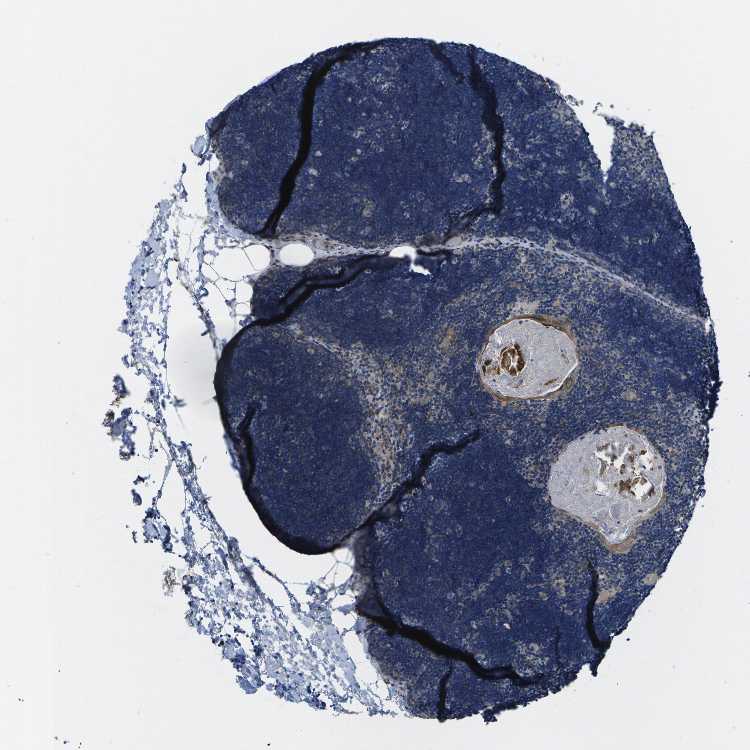

TISSUE PRIMARY DATA LYMPH NODE Show tissue menu

Lymph node

Tissue proteome

Lymphoid tissue

LYMPH NODE - Expression summary

Protein expression

Lymph nodei

On the top, protein expression in current human tissue, based on all annotated cell types, is reported with the units not detected (n), low (l), medium (m) and high (h). Underneath, protein expression in each annotated cell type are reported using the same units.

Protein expression data is based on knowledge-based annotation. For genes where more than one antibody has been used, a collective score is set.

If knowledge-based annotation could not be performed for a gene, no data is displayed here. View antibody staining data further down this page.

LYMPH NODE - Antibody stainingi

Antibody staining in the annotated cell types in the current human tissue is reported as not detected, low, medium, or high, based on conventional immunohistochemistry profiling in selected tissues. This score is based on the combination of the staining intensity and fraction of stained cells.

Each image is clickable and will lead to virtual microscopy that enables deeper exploration of all samples and also displays staining intensity scores, fraction scores and subcellular localization as well as patient and tissue information for each sample.

Antibody HPA012113Antibody HPA016980

Germinal center cells LowNot detected

Non-germinal center cells LowNot detected